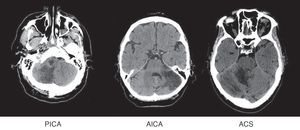

Se ha dividido a los pacientes según el territorio afectado, siguiendo los diagramas de Amarenco14: arteria cerebelosa superior (ACS), arteria cerebelosa anteroinferior (AICA), arteria cerebelosa posteroinferior (PICA), más de un territorio cerebeloso afectado (ACx) y afectación simultánea de territorios supratentoriales (ST) (fig. 1).

La afectación territorial, por orden de prevalencia, ha sido: 61 PICA (49,2%), 22 ACS (17,7%) y 13 AICA (10,5%). 11 pacientes pertenecen al grupo ACx (8,9%) y 17 (13,7%) tenían afectación simultánea de territorios supratentoriales.